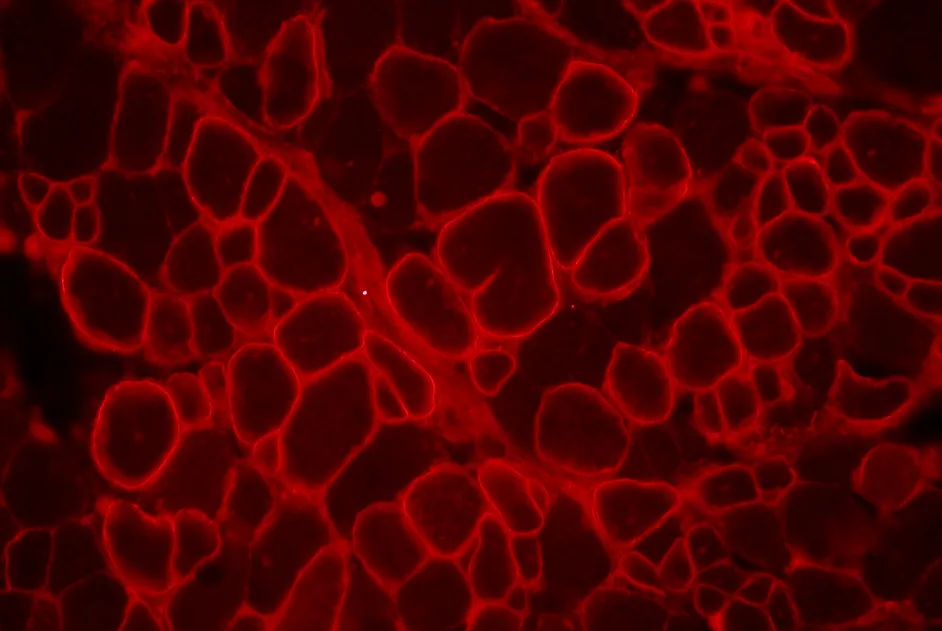

Il faut une dose suffisante d’AAV-U7 pour restaurer l’expression de la dystrophine des muscles dystrophiques traités sans disparaitre.